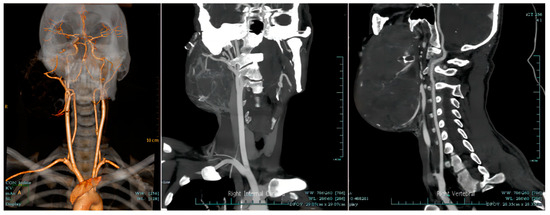

| Radiology | CTA is recommended when necessary to clarify the relationship between the tumor and neck vessels. |

| Neurosurgery | If the tumor has a rich blood supply from right external carotid artery, preoperative external carotid artery embolization can be considered to prevent intraoperative bleeding. |